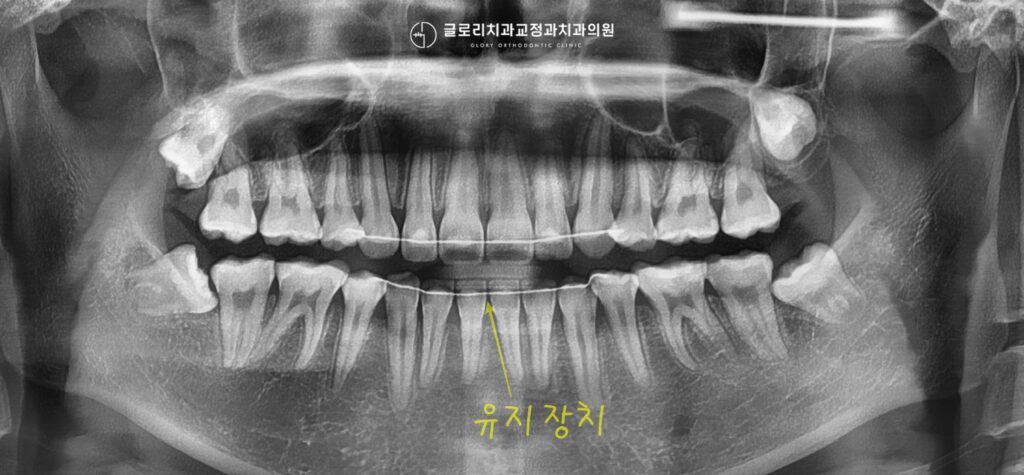

우리 치아는 다시 원래의 자리로 돌아가려는 성질을 갖고있는데요.

치아가 다시 움직이지 않도록 반드시 유지장치를 사용하도록 합니다.